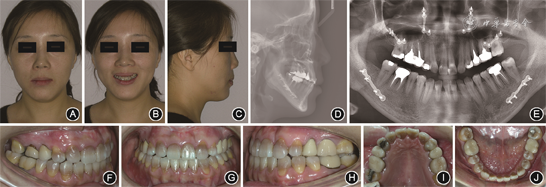

成年患者正颌术前面像、口内像和影像学资料 A:正面像;B:正面微笑像;C:侧面像;D:头颅侧位X线片;E:曲面体层X线片;F:右侧

像;G:正面

像;H:左侧

像;I:上颌

面像;J:下颌

面像

面像(2)正颌手术:正颌手术采用双颌手术。上颌行Le Fort Ⅰ型截骨术,前徙上颌骨,于双侧梨状孔边缘和双侧颧牙槽嵴处分别以2块“L”型微型钛板、8枚微型螺钉固定。下颌行双侧矢状劈开截骨后退术,于双侧外斜线处以2块小型钛板、8枚微型螺钉固定。